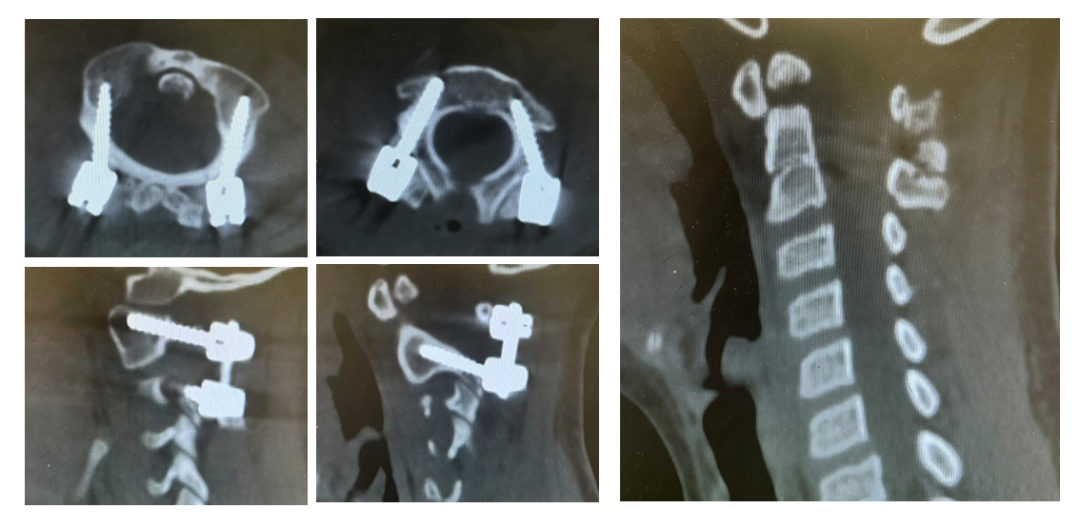

手术日,在麻醉与神经电生理监测团队的全程护航下,主刀医生许正伟主任首先巧妙利用颅骨牵引,为完全脱位的关节实现了初步松解与部分复位。随后,在高端术中导航系统(S8)的实时引导下,将椎弓根螺钉精准、安全地置入寰椎与枢椎的微小椎弓根内。利用螺钉提供的稳固杠杆,脱位的关节被轻柔而坚定地“推”回了正常解剖位置,实现了完美复位。最后,取自患儿自身的髂骨块被植入后方,为永久性骨融合打下基础。

术后影像显示:脱位完全矫正,内固定位置精确无误。次日,在康复师指导下,康康便戴着支具成功坐起。母亲眼中的担忧化为惊喜的泪光。术后第三天,引流管顺利拔除,伤口愈合良好。康康不再拿手抱着颈部,开始戴着支具下地。